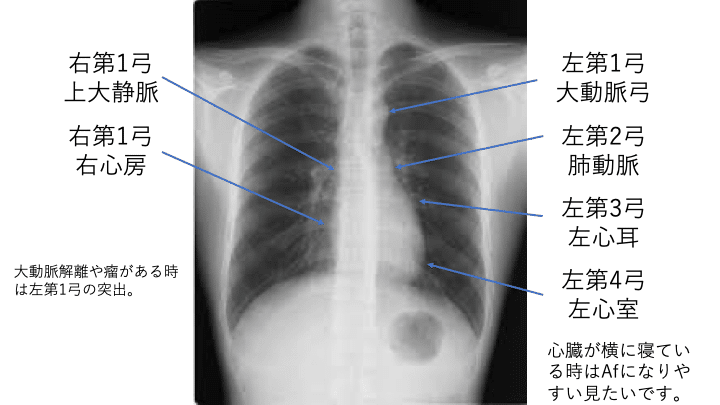

大北 裕/Yutaka Okita – 岐阜ハートセンター。第1回 講演会 神戸大学心臓血管外科 大北裕教授 2016/11/4。胸部Xpについて|Masayuki Nishiyama。胸部大動脈に関する専門的な外科手術の解説書。⚠︎電子書籍にするため、裁断しておりますのでご注意ください。本の質的と、分厚いので綺麗に揃えるのが難しいことご了承ください。- 書名: Surgery for the Thoracic Aorta- 著者: 大北 裕- 言語: 日本語- 出版社: 南江堂- ジャンル: 医学- 状態: カバーに小さな傷み、やぶれあり。✳︎2023年購入。ご覧いただきありがとうございます。。人体の正常構造と機能。[裁断済]脳卒中ハンドブック第4版。犬と猫の実践 細胞診アトラス。[医学書院] 看護学 看護師 看護学生 教科書 参考書。【裁断済】dAVF・AVM (脳動静脈奇形) のすべて。週刊ダイヤモンド 2021年9月14日号

• 第1回 講演会 神戸大学心臓血管外科 大北裕教授 2016/11/4

• 胸部Xpについて|Masayuki Nishiyama